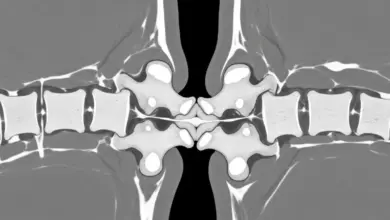

- A radiografia anteroposterior da coluna lombossacra costuma identificar a vértebra de transição.

- A tomografia detalha a anatomia óssea quando necessário.

- A ressonância magnética avalia o disco e sinais de inflamação nas articulações.